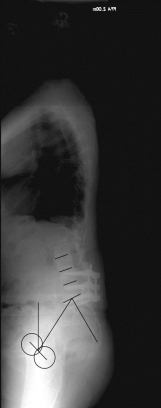

X-ray image before and after surgery. The patient underwent spinal surgery at another hospital and increasingly developed other complaints. The X-ray showed a complete loss of the hollow back and a resulting change in balance. A so-called lordosis operation led to a restoration of a normal hollow back and thus a normal spinal balance and finally to regressive complaints.